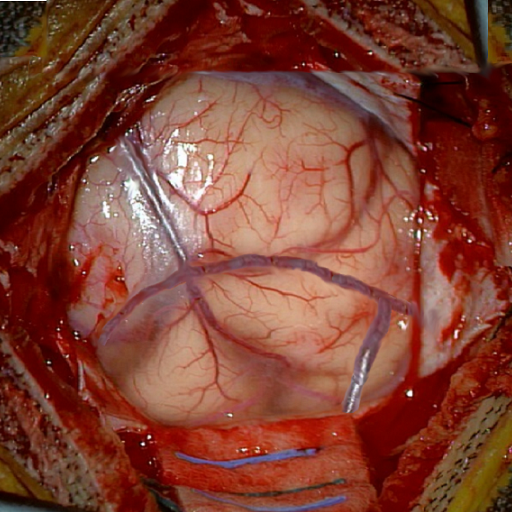

We tested our method retrospectively on 6 clinical datasets from 6 patients (cases) (see Fig. 5). These consisted of preoperative T1 contrast MRI scans and intraoperative images of the brain surface after dura opening. Cortical vessels around the tumors were segmented and triangulated to generate 3D meshes using 3D Slicer. We generated 100 poses for each 3D mesh (i.e.: each case) and used a total of 15 unique textures from human brain surfaces (different from our 6 clinical datasets) for synthesis using . In order to account for potential intraoperative brain deformations [4] we augment the textured projection with elastic deformation [21] resulting in approximately 1500 images per case. The surgical images of the brain (left image of the stereoscopic camera) were acquired with a Carl Zeiss surgical microscope. The ground-truth poses were obtained by manually aligning the 3D meshes on their corresponding images.

Fig. 5 shows our results as Augmented Reality views with bounding boxes and overlaid meshes. Our method produced visually consistent alignments for all 6 clinical cases without the need for initial registration. Because our current method does not account for brain-shift deformation, our method produced some misalignment errors. However, in all cases, our predictions are similar to the ground truth.